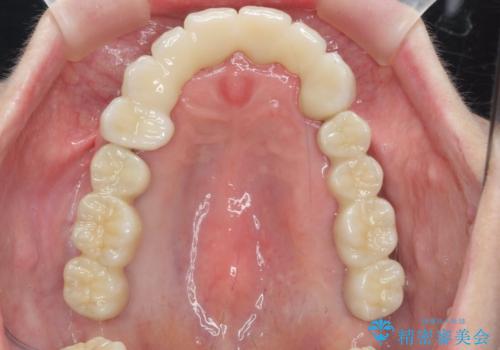

多発した虫歯による咬合崩壊 インプラントを用いた全顎治療

歯の破折・再発した大きな虫歯・根尖病変・歯の欠損、これらの問題を根管治療・歯周外科・インプラント治療・セラミック補綴を行うことで一つづつ解決し安定した咬合状となるよう治療を進めます。

治療に加えて歯ブラシも上手になることが、治療した歯を長持ちさせるのに必要な要件となります。